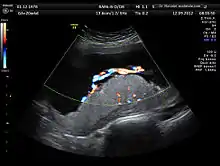

A 3D Power doppler image of vasculature in 20-week placenta